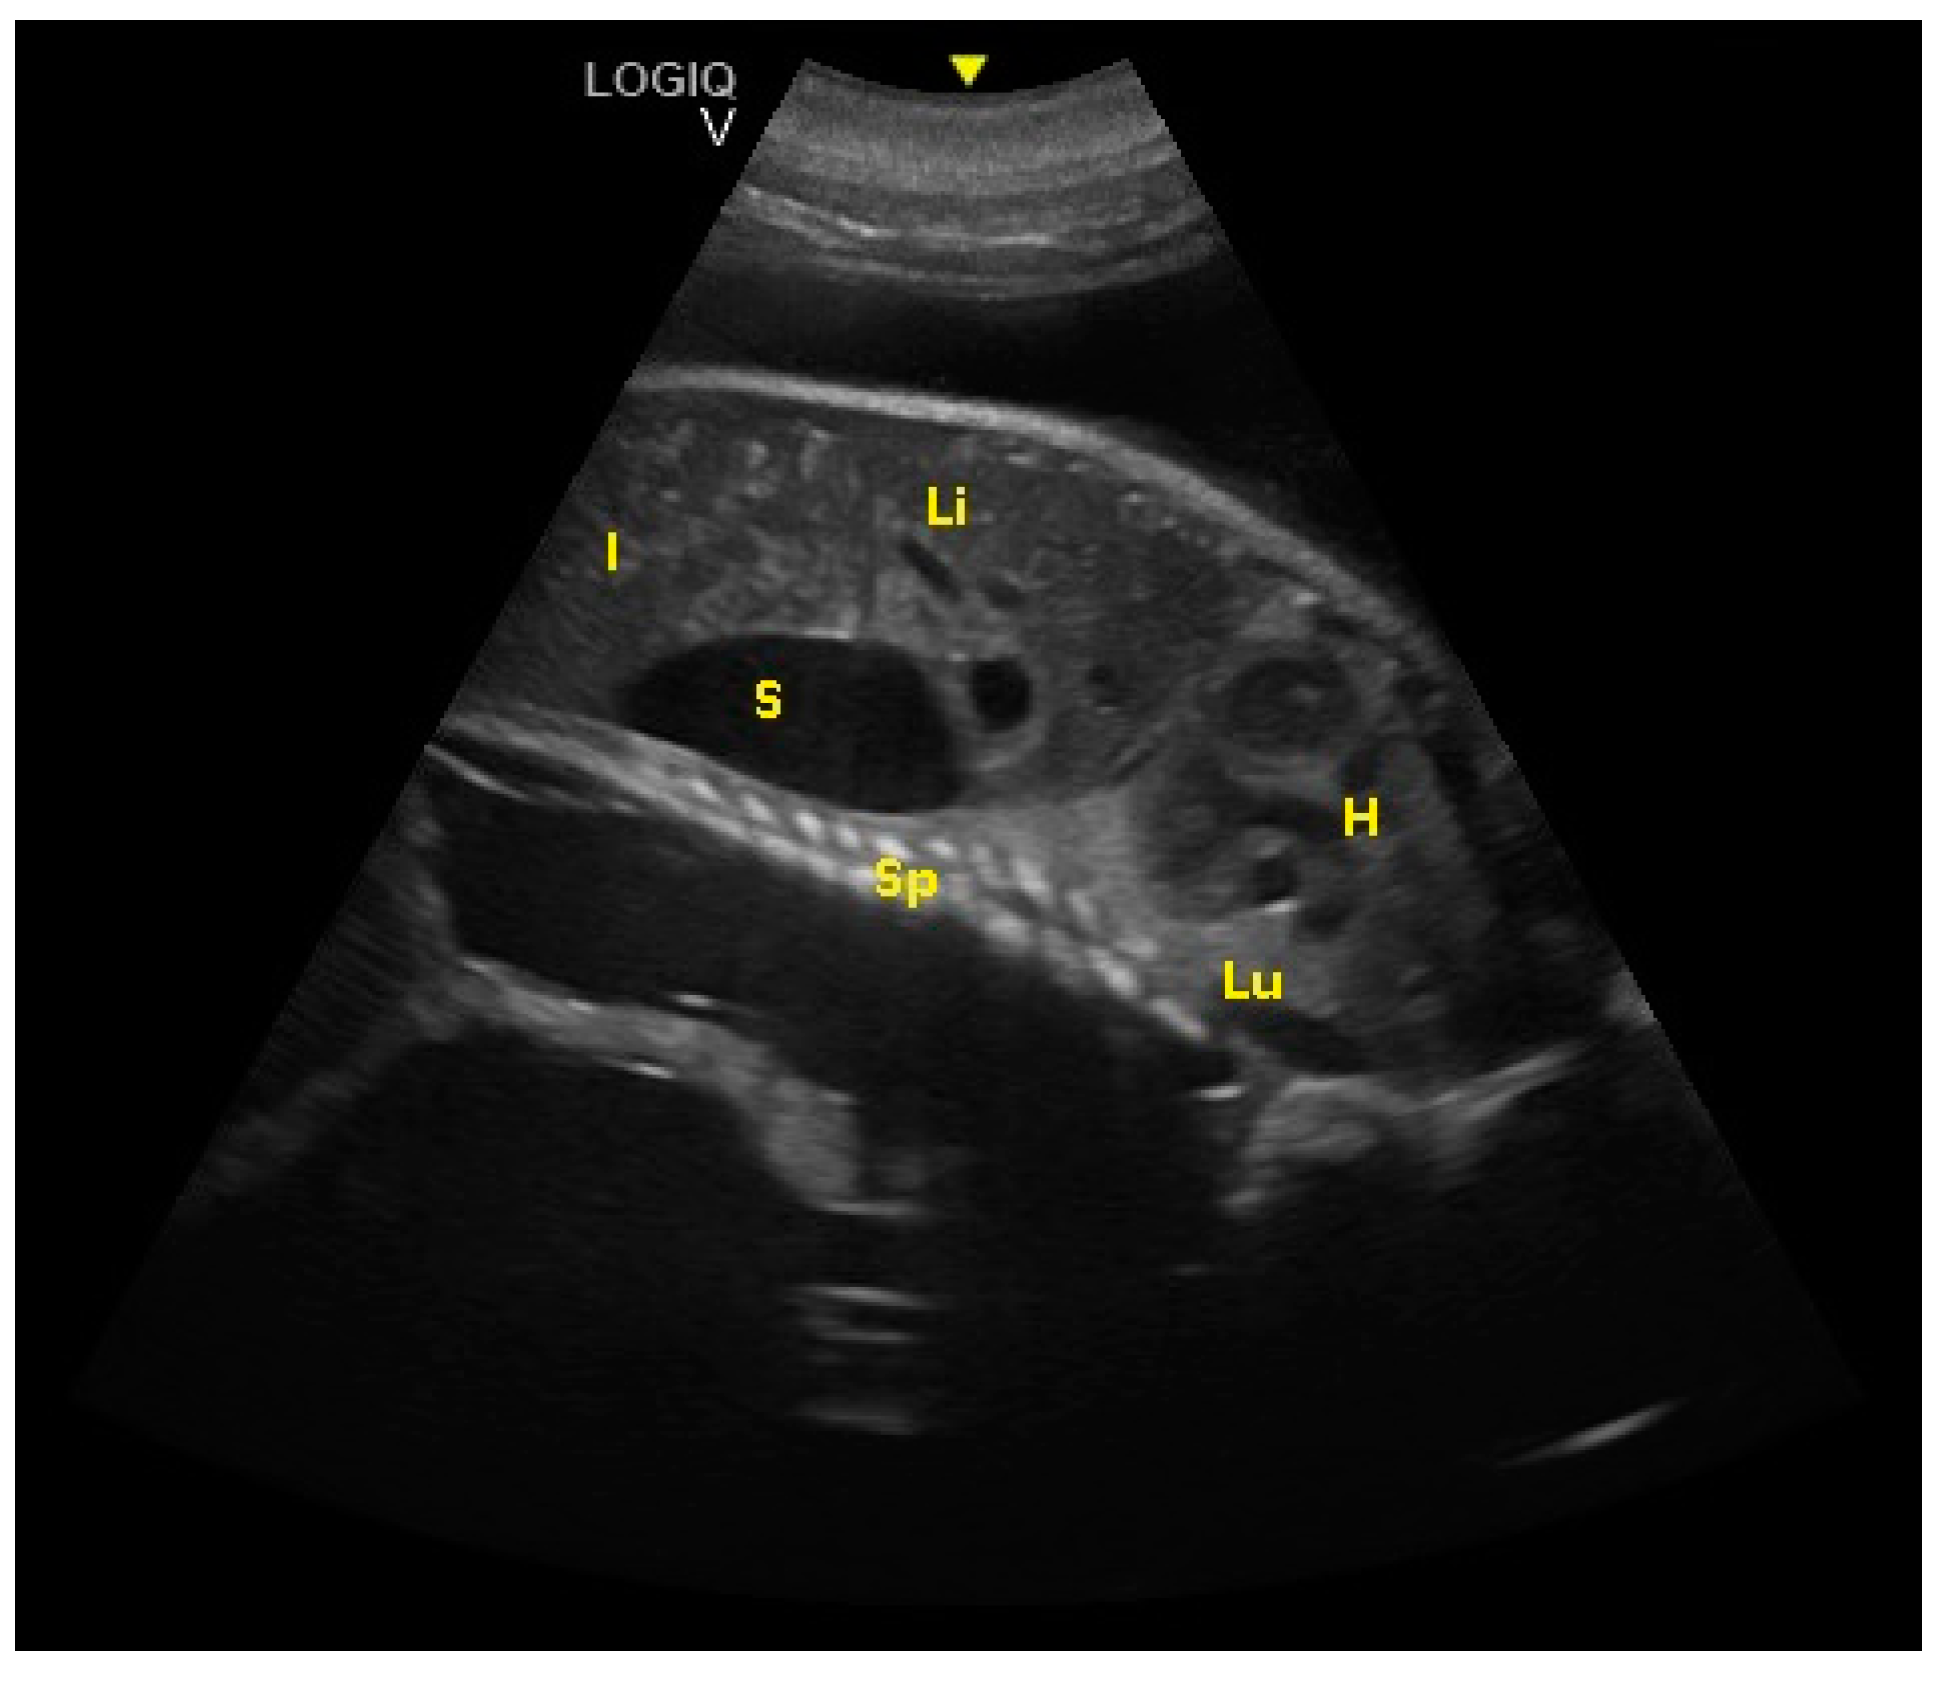

The intestine was visualized at 189 ± 5 days of gestation. The cardiac chambers were visualized 194 ± 5 days after ovulation, and after about 3 weeks, the vascular structures (aorta and caudal vena cava) departing from them were visualized (Figure 7).

Figure 7.

Fetal spinal cord (Sp), stomach (S), liver (Li), intestine (I), lungs (Lu), and heart (H) were visualized at 194 ± 5 days of gestation.